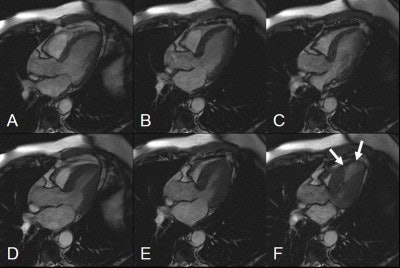

![]() |

| A 42-year-old male patient after large myocardial infarction. Top, diastolic (left) and systolic (right) TrueFISP Cine images in LVOT orientation. Arrows show a large akinetic area in the anteroseptal wall. Bottom, IR-TurboFLASH image done 10 minutes after administration of gadolinium. The bright area shows transmural infarction (late enhancement) of the anteroseptal, apical and inferolateral wall. Asterisk shows a small akinetic area without late enhancement in the basal anteroseptal wall. |